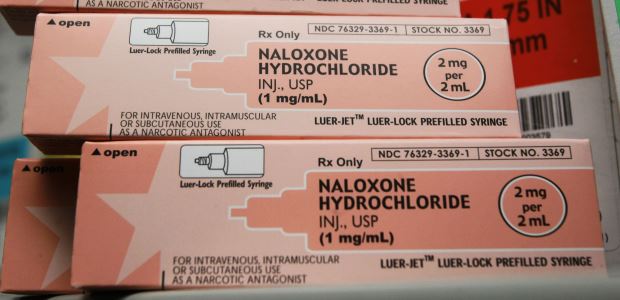

"There's nothing like MATx in the field today," said SAMHSA Principal Deputy Administrator Kana Enomoto. "It will be a significant step forward in improving timely access to medication-assisted treatment by enabling physicians and other health care practitioners to better provide effective, evidence-based, and in some cases, life-saving treatment to people with opioid use disorders."